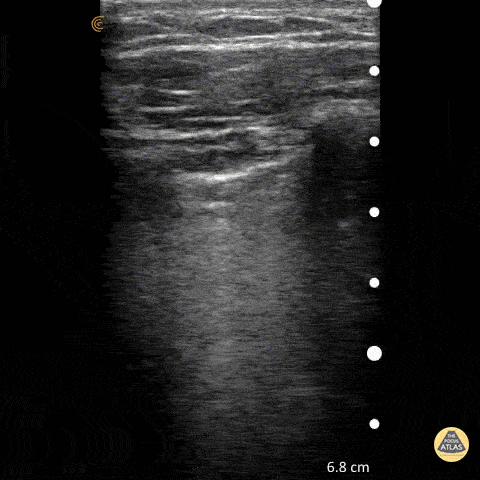

Pulmonary - Normal Lung Slide

To assess for lung slide, look between two ribs. The two layers of pleura can be seen as the hyperechoic, shimmering line just under the subcutaneous tissue. This represents the sliding of the parietal and visceral pleura. Normal lung slide should have: Shimmering aka "ants marching" This may be augmented by m-mode as pictured in another post. Dr. Matthew Riscinti - Kings County Emergency Medicine